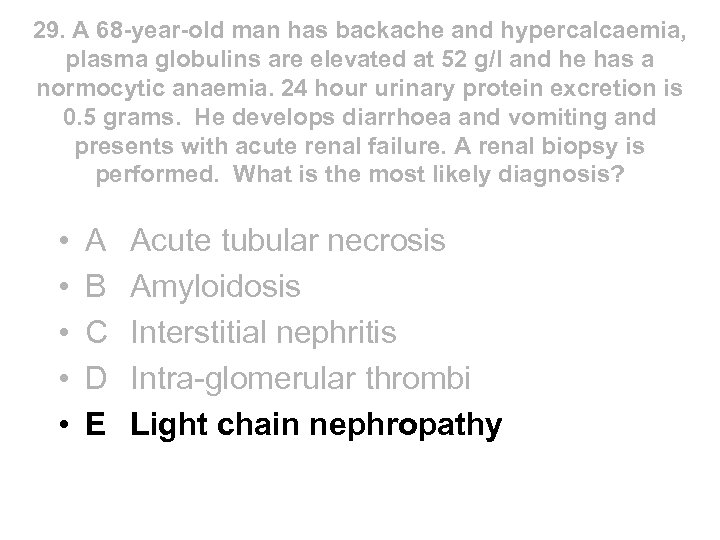

29. A 68 -year-old man has backache and hypercalcaemia, plasma globulins are elevated at 52 g/l and he has a normocytic anaemia. 24 hour urinary protein excretion is 0. 5 grams. He develops diarrhoea and vomiting and presents with acute renal failure. A renal biopsy is performed. What is the most likely diagnosis? • • • A B C D E Acute tubular necrosis Amyloidosis Interstitial nephritis Intra-glomerular thrombi Light chain nephropathy

29. A 68 -year-old man has backache and hypercalcaemia, plasma globulins are elevated at 52 g/l and he has a normocytic anaemia. 24 hour urinary protein excretion is 0. 5 grams. He develops diarrhoea and vomiting and presents with acute renal failure. A renal biopsy is performed. What is the most likely diagnosis? • • • A B C D E Acute tubular necrosis Amyloidosis Interstitial nephritis Intra-glomerular thrombi Light chain nephropathy

29. A 68 -year-old man has backache and hypercalcaemia, plasma globulins are elevated at 52 g/l and he has a normocytic anaemia. 24 hour urinary protein excretion is 0. 5 grams. He develops diarrhoea and vomiting and presents with acute renal failure. A renal biopsy is performed. What is the most likely diagnosis? • • • A B C D E Acute tubular necrosis Amyloidosis Interstitial nephritis Intra-glomerular thrombi Light chain nephropathy

29. A 68 -year-old man has backache and hypercalcaemia, plasma globulins are elevated at 52 g/l and he has a normocytic anaemia. 24 hour urinary protein excretion is 0. 5 grams. He develops diarrhoea and vomiting and presents with acute renal failure. A renal biopsy is performed. What is the most likely diagnosis? • • • A B C D E Acute tubular necrosis Amyloidosis Interstitial nephritis Intra-glomerular thrombi Light chain nephropathy

Myeloma • Aetiology of renal failure • - nephrotoxicity due to free light chains • - also dehydration, hypercalcaemia, infection, amyloid, hyperuricaemia • Presentation • - AKI or CRF • - Hypercalcaemia and low platelets are important clues to diagnosis in renal failure • Diagnosis • - 10% clonal bone marrow plasma cells plus • - Monoclonal protein in serum or urine plus/minus • - Myeloma related organ dysfunction: hypercalcaemia, renal insufficiency, anaemia, bone disease (lytic lesions) • - renal biopsy not mandatory, usually shows light chain nephropathy

Myeloma • Aetiology of renal failure • - nephrotoxicity due to free light chains • - also dehydration, hypercalcaemia, infection, amyloid, hyperuricaemia • Presentation • - AKI or CRF • - Hypercalcaemia and low platelets are important clues to diagnosis in renal failure • Diagnosis • - 10% clonal bone marrow plasma cells plus • - Monoclonal protein in serum or urine plus/minus • - Myeloma related organ dysfunction: hypercalcaemia, renal insufficiency, anaemia, bone disease (lytic lesions) • - renal biopsy not mandatory, usually shows light chain nephropathy